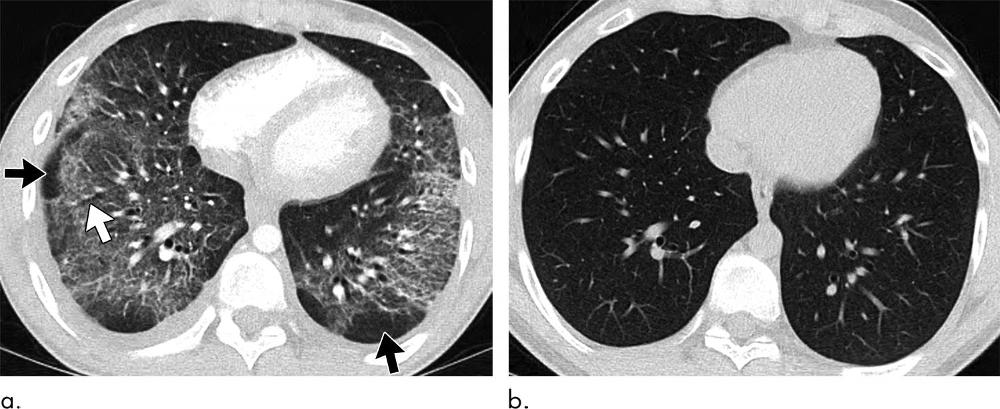

Figure 5. Images show electronic cigarette or vaping product use–associated lung injury with organizing pneumonia pattern in a 20-year-old man who vapes nicotine and tetrahydrocannabinol products daily and who presented to community health clinic with fever, weakness, and chills. He was initially diagnosed with community-acquired pneumonia, but his symptoms continued to progress despite antibiotic therapy. Extensive work-up for infection and rheumatologic disease was negative during hospital admission. (a) Axial CT image shows peribronchiolar ground-glass opacity with subpleural sparing both centrally and peripherally (black arrows). Few areas of bronchial dilation are present in areas of ground-glass opacity (white arrow). Bronchoscopic biopsy yielded result of organizing pneumonia. (b) Four weeks after initiation of steroid therapy, patient’s CT scan was normal.

High-res (TIF) version